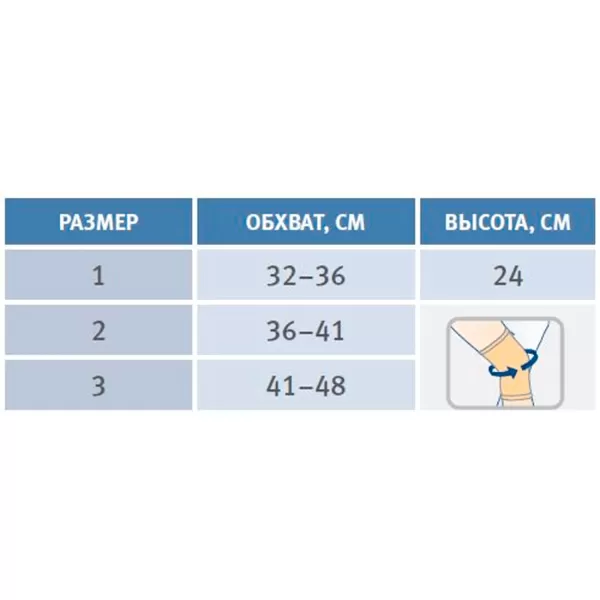

| Материал | Полиэстер 100%, Металлические рёбра, Полотно велюр, Застёжка пластик |